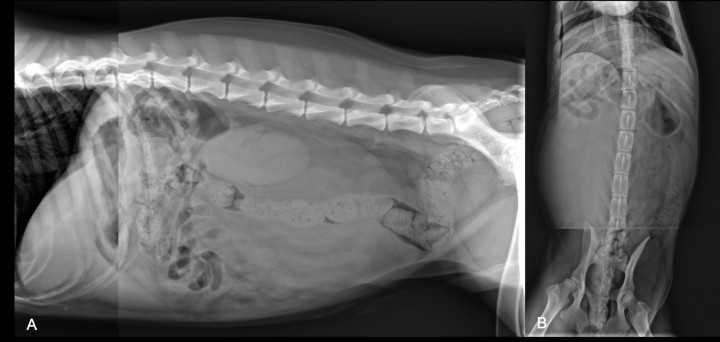

Se presenta en consulta un Golden Retriever de 1 año, macho no castrado, con un cuadro de hematuria e infecciones de orina recurrentes desde cachorro, manejadas con antibioterapia. Actualmente en tratamiento con ciprofloxacino. La exploración general y el hemograma son normales, observándose únicamente niveles bajos de globulinas (2,5 g/dl; referencia: 2,8-5,1 g/dl), urea (13,8 mg/dl; referencia: 16-36 mg/dl) y fósforo (2,32 mg/dl; referencia: 3,1-7,5 mg/dl) en la bioquímica. Se realizan radiografías de abdomen lateral derecha (LLD) y ventrodorsal (VD), en dos secciones (abdomen craneal y caudal) debido al gran tamaño del paciente (Fig. 1).

<p>Radiografías del abdomen tomadas en dos secciones (debido al gran tamaño del animal). (<strong>A</strong>) Proyección lateral derecha. (<strong>B</strong>) Proyección ventrodorsal.</p>

Radiografías del abdomen tomadas en dos secciones (debido al gran tamaño del animal). (A) Proyección lateral derecha. (B) Proyección ventrodorsal.